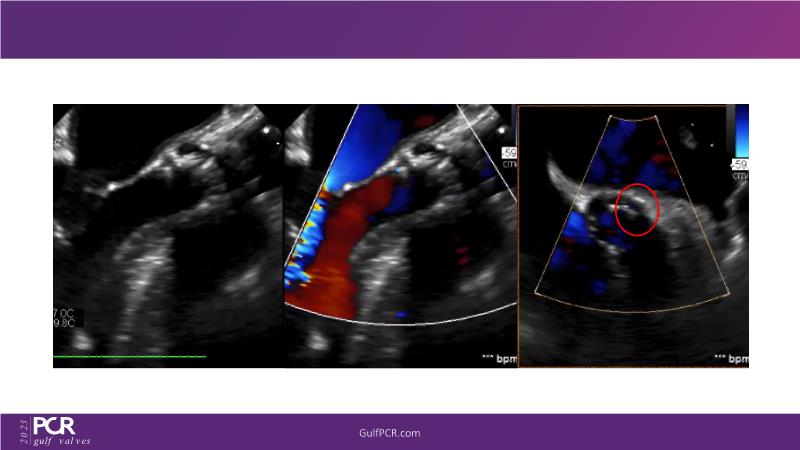

The primary focus of this GulfPCR-GIM 2023 session revolves around pre-procedural planning considerations, valve selection, and managing complex anatomies using both traditional self-expanding valves and the Evolut FX system. Additionally, the session aims to explore the work-up protocol for patients grappling with severe AS and advanced CKD, elucidate the algorithm for selecting the appropriate TAVR platform, discuss strategies to reduce contrast utilization, and highlight the distinctive advantages offered by the Evolut FX system.

• To discuss challenges in TAVI procedural planning

• To discuss valve choice in challenging anatomies